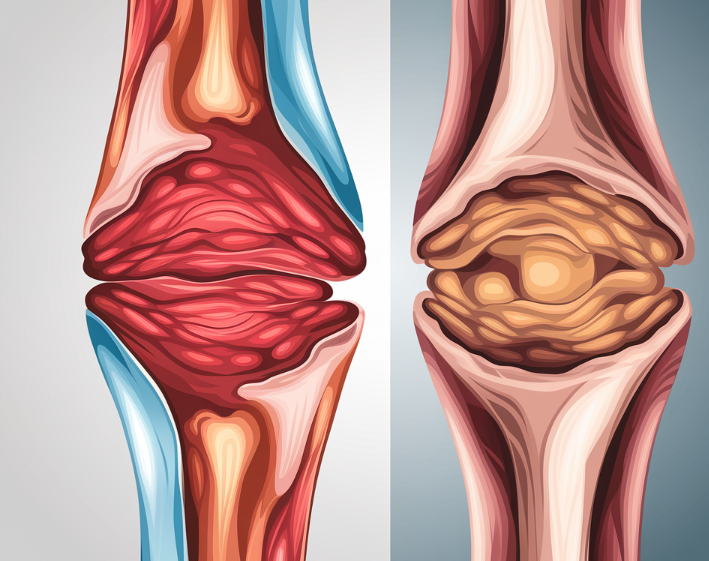

3. 염증 완화

- EPA는 염증을 줄이고 관절 건강에 도움을 줍니다.